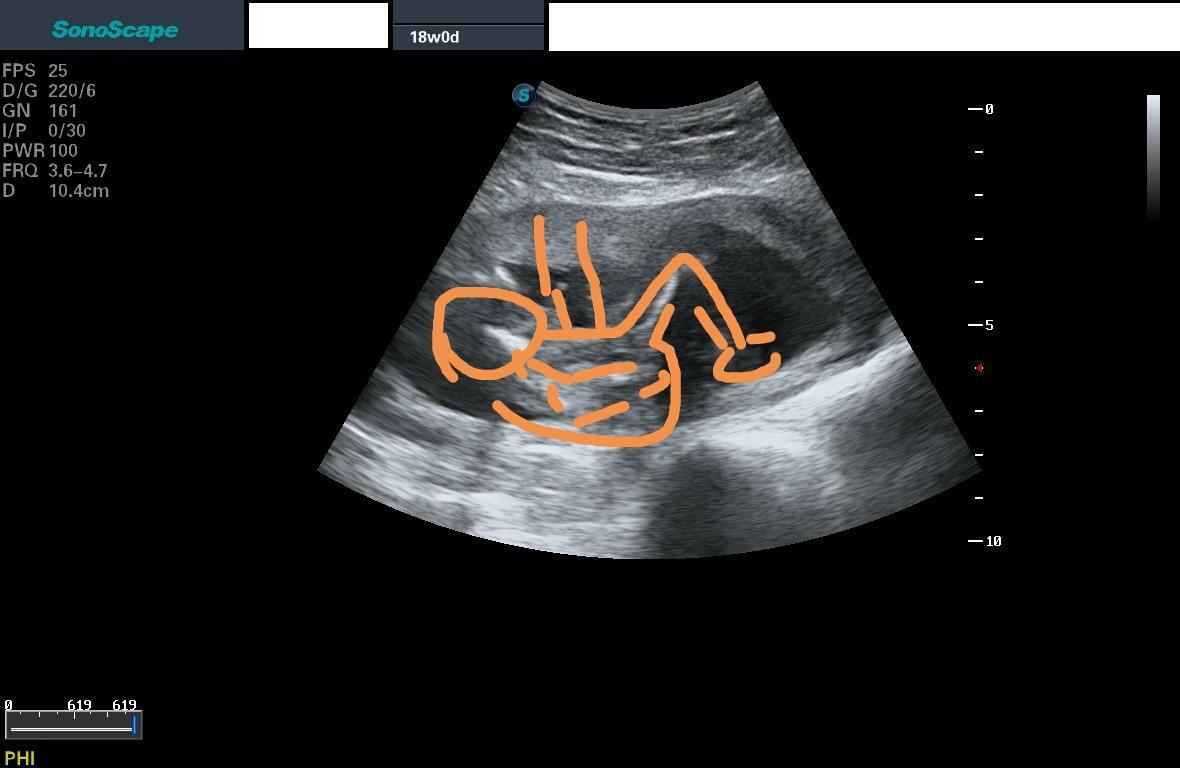

na flashku mi doktor v 18. týdnu těhotenství nahrál několik fotek z ultrazvuku a já nemůžu přijít na to, co je na téhle 😀 přijde mi to jen jako změť fleků. Co byste řekli, že to je? Nějaký detail?

Ja bych rekla lezici miminko, vlevo hlavicka, to vyrazny rucicky, takovy to vroubkovany nahoru pupecnik a pak nozky 🙂

Zkusila jsem to nacrtnout v mobilu, moc to nejde :D

Jak rika @petruuushkaaa 🙂 presne, levo hlavicka, pak kousek doprava rucicka a pokrcena nozicka tvar ^ 🙂

já ještě myslela, jestli to není detail pohlaví, ale ani to se mi moc nezdálo, protože jsem tam nikde neviděla nohy 😀